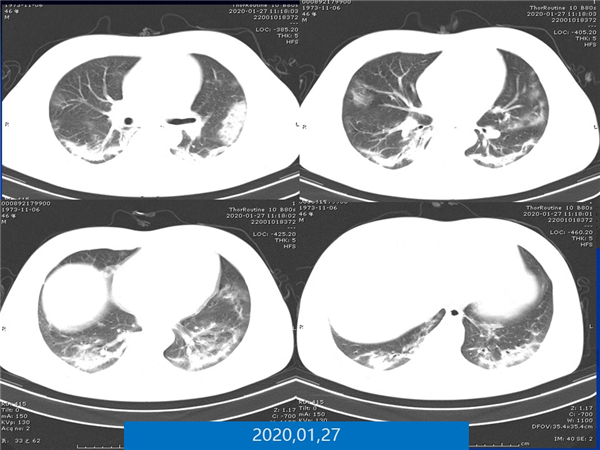

【病例分享】新型冠狀病毒感染肺部CT影像4例(常德市第一人民醫(yī)院)